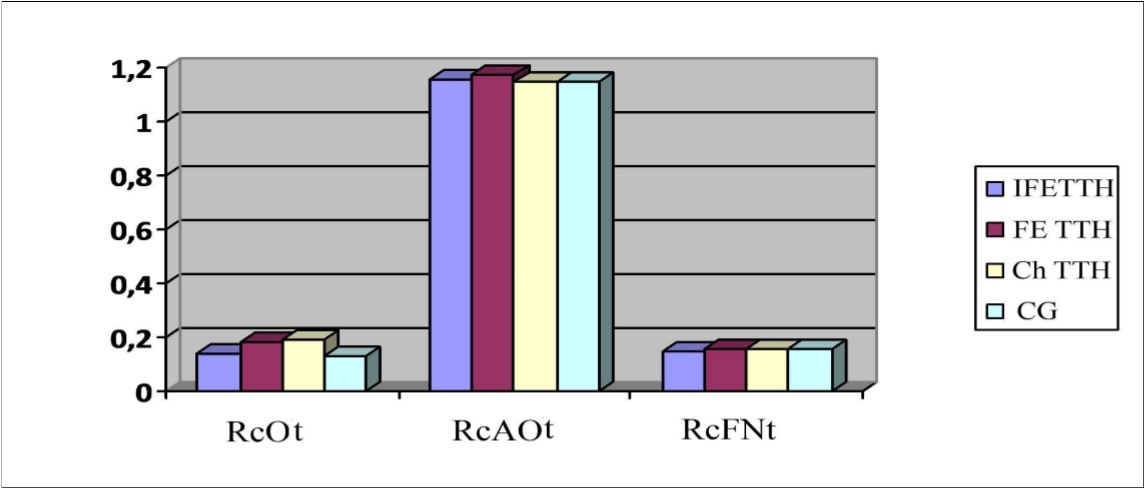

As can be seen from Figure 4 similar results were obtained with the antiorthostatic test (RcAOt) compared with the results of the orthostatic (RcOt) and functional test with nitroglycerin (RcFNt). However, in the study of reactivity to orthostatic, nitroglycerin and antiorthostatic tests there were no significant differences between the parameters of patients with IF TTH, FE TTH, Ch TTH and CG.

Figure 4.Parameters of reactivity coefficient (Rc) to the orthostatic test (Ot), antiorthostatic test (AOt) and functional nitroglycerin test (FNt) in a patients with TTH.

When performing orthostatic and hypercapnic load, a similar (identical) auto-regulating effect of Noofen on vascular reactivity was found. The initially increased RcOt in patients with FETTH decreased from 0.18±0.03 to 0.14±0.2 and from 0.19±0.04 to 0.14±0.03 in patients with ChTTH. No significant changes were observed in initially close to the normative indicators in patients with IFETTH, which once again confirms the selectivity of the influence of Noofen on the mechanisms of vascular autoregulation. A similar picture was characteristic of the initially close to the standard parameters of RcAOt and RcFNt (Figure 11).